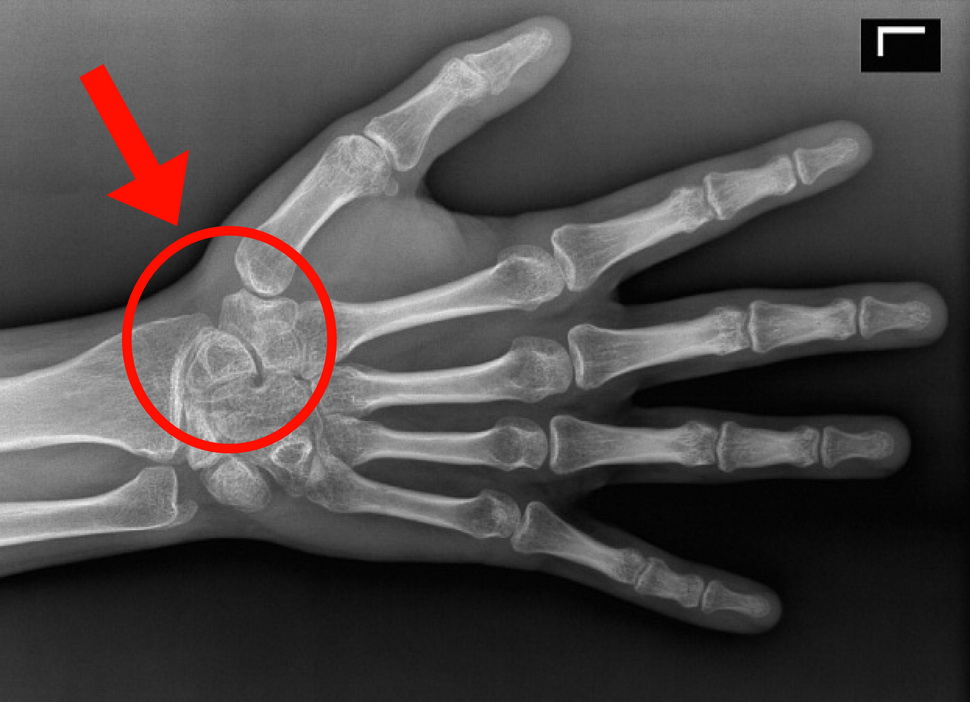

Подборка рентгеновских снимков лучезапястного сустава

Раздел: Объективный взгляд